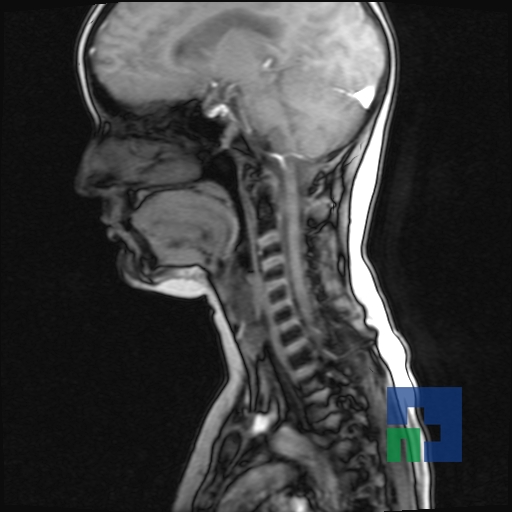

Examinare de rutină cerebrală, nativ și cu substanță de contrast (SDC) pentru diagnosticul:

- Accidentelor vasculare cerebrale ischemice sau hemoragice

- Tumorilor cerebrale

- Tumorilor cerebrale:

- Atrofia cerebrală regională